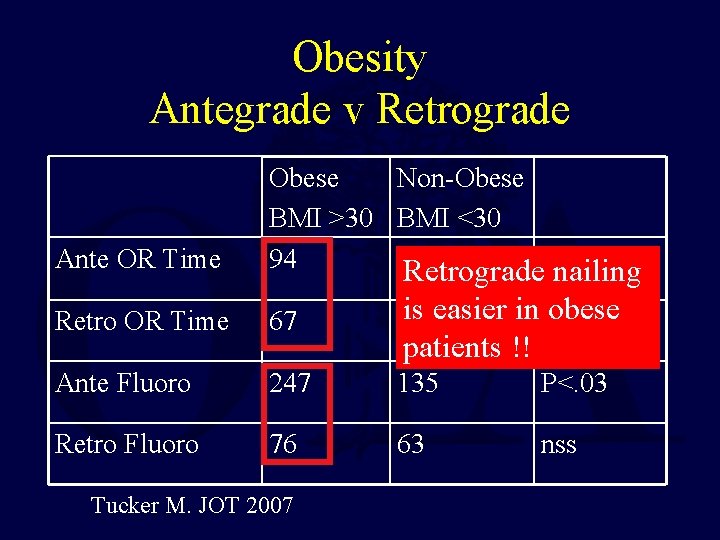

Obesity Antegrade v Retrograde Ante OR Time Obese Non-Obese BMI >30 BMI <30 94 62 P<. 003 Retrograde nailing Retro OR Time 67 is easier in nss obese 62 Ante Fluoro 247 135 P<. 03 Retro Fluoro 76 63 nss Tucker M. JOT 2007 patients !!